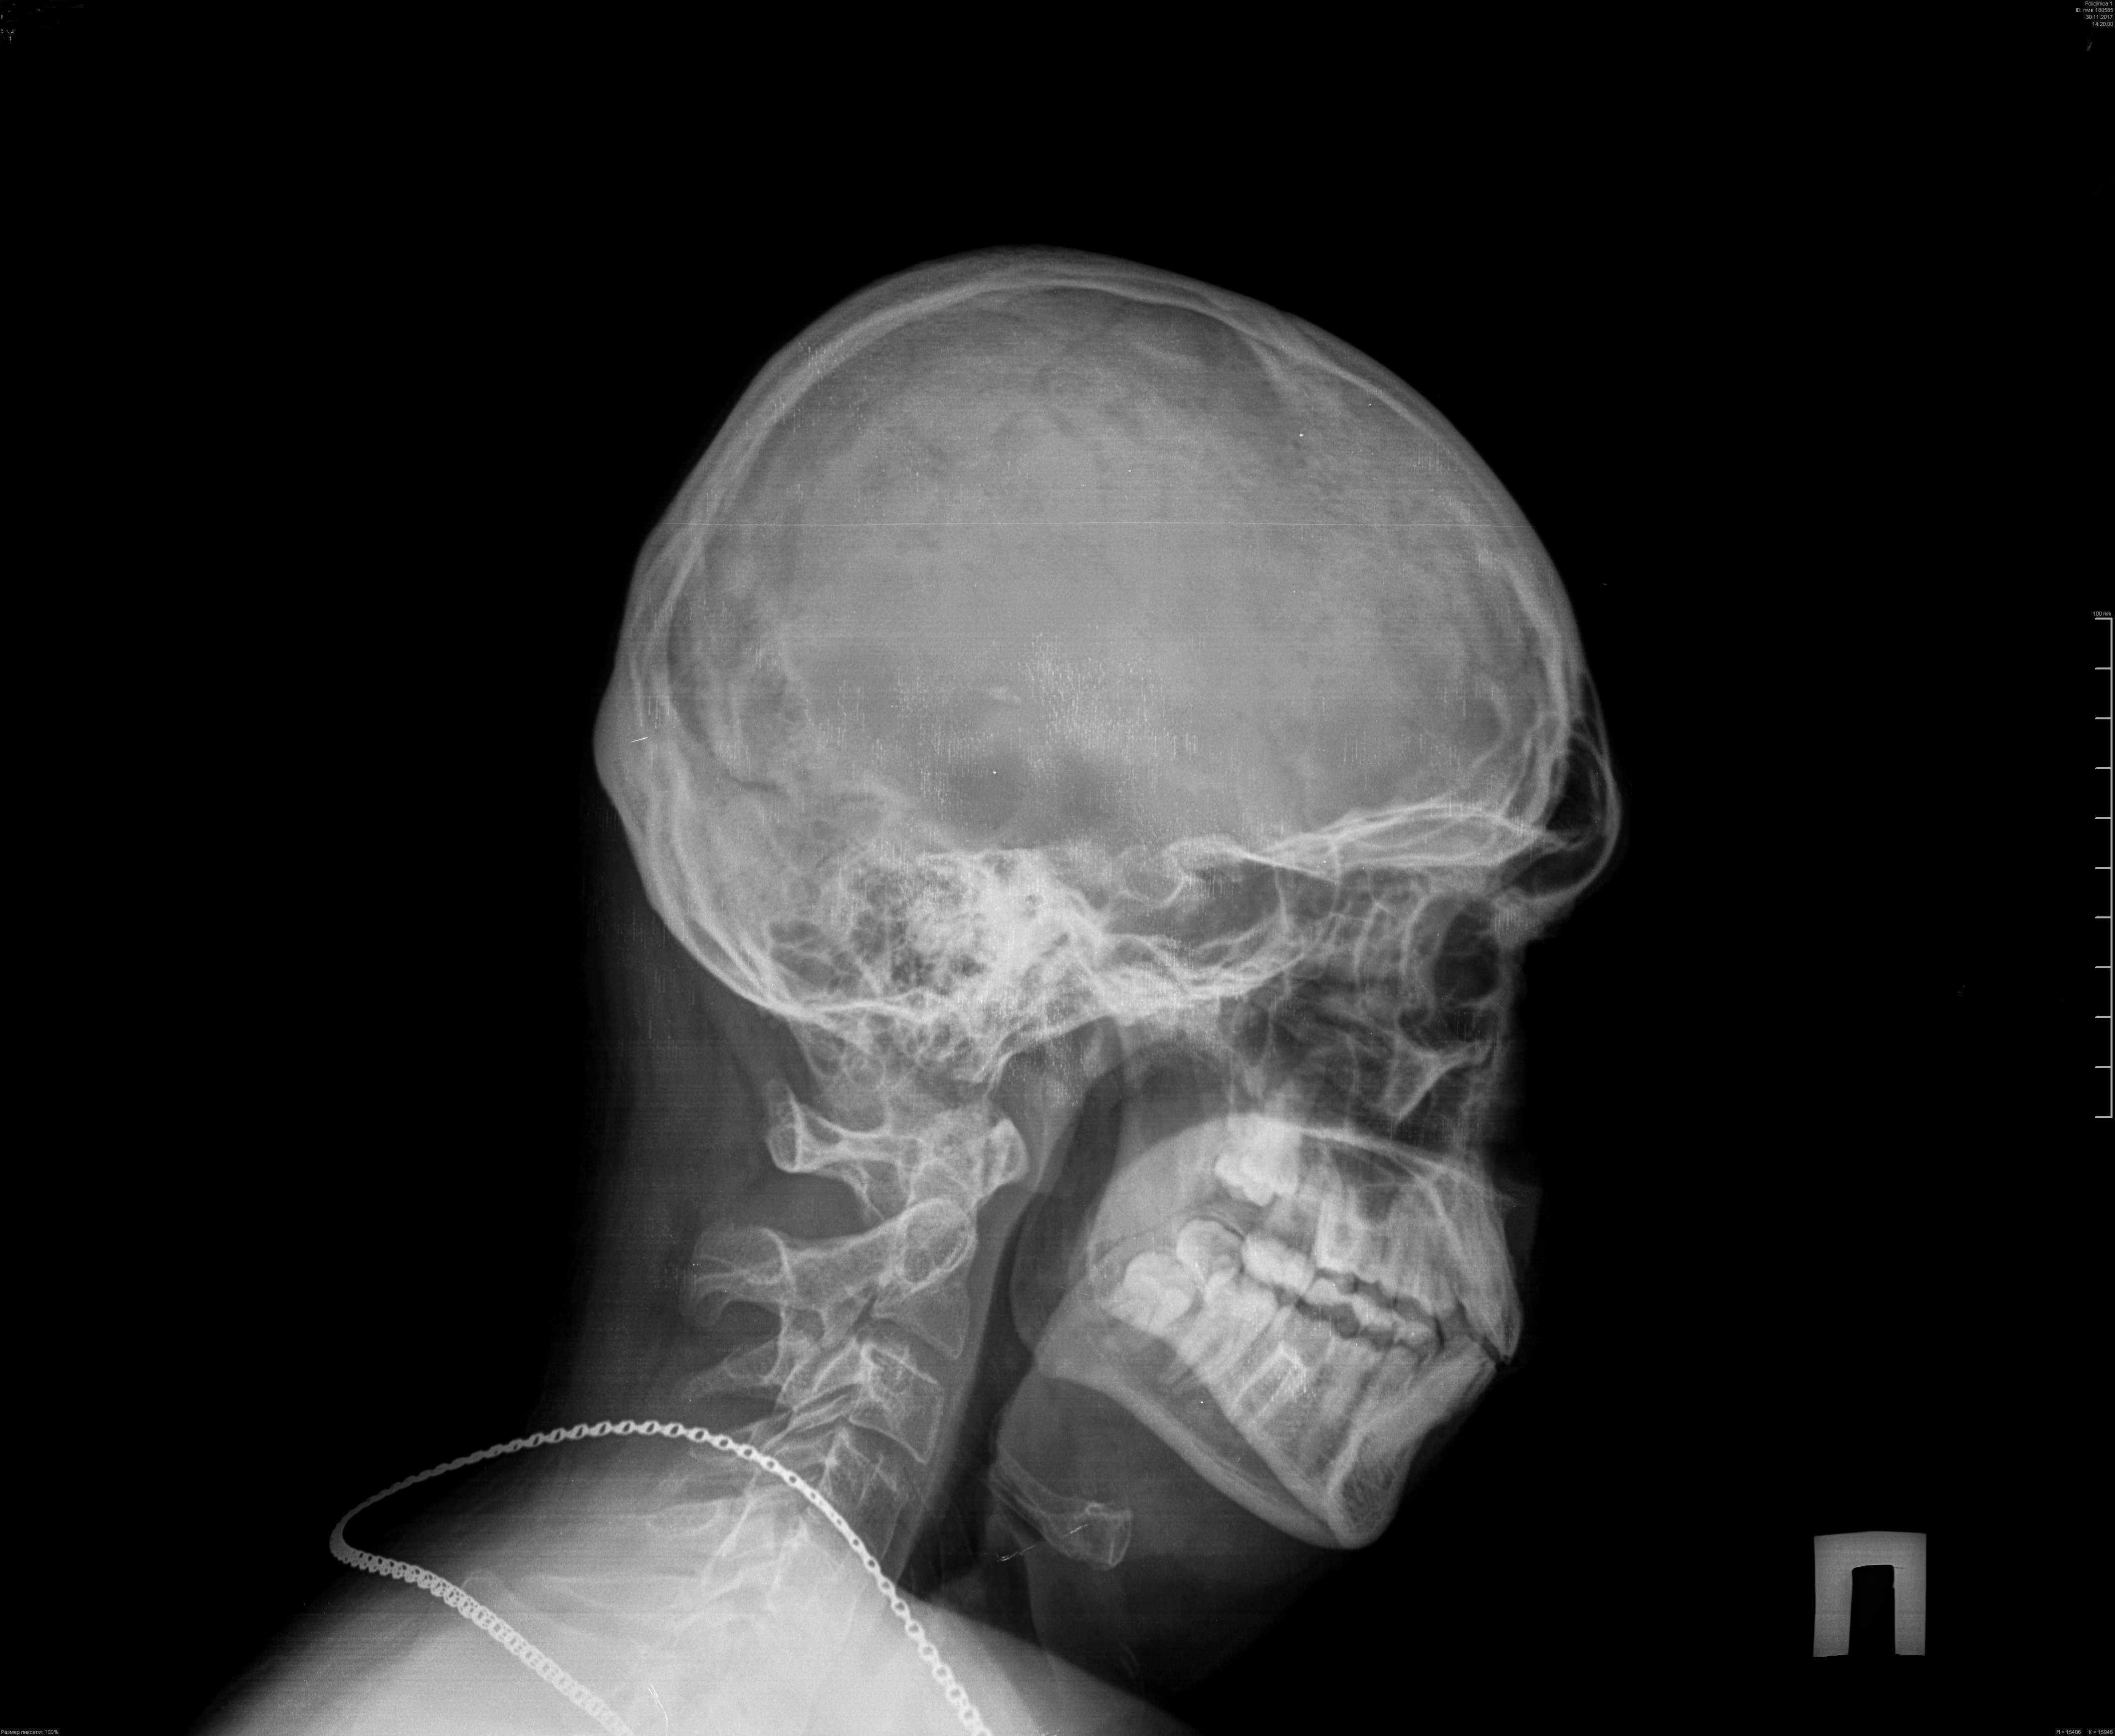

Рентгенография черепа и позвоночника: изображение и диагностика